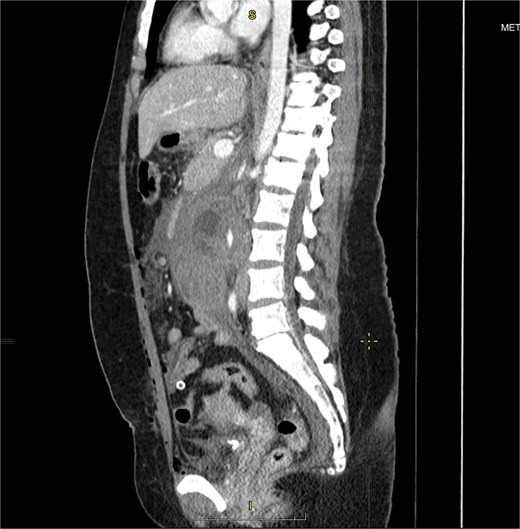

She underwent abdominal sonography followed by contrast-enhanced computed tomography (CECT). Both demonstrated a right-sided retroperitoneal hematoma adjacent to the inferior vena cava and right kidney. A 5 cm ring-shaped structure resembling an empty gestational sac was detected inside the hematoma (Fig. 1). CT showed contrast extravasation representing active bleeding (Figs 2 and 3). Interdisciplinary team discussion, including obstetrician-gynecologists, abdominal surgeons, anesthesiologists, and radiologists, led to the decision for emergency relaparotomy.

Venous phase coronal plane CECT of the abdomen and pelvis demonstrates a large right-sided retroperitoneal hematoma with a central cystic structure, consistent with a gestational sac. A focus of contrast extravasation is visible medial to the sac. The * symbol denotes blood tracing along the ovarian vessels toward the right pelvic wall, also seen on surgery.